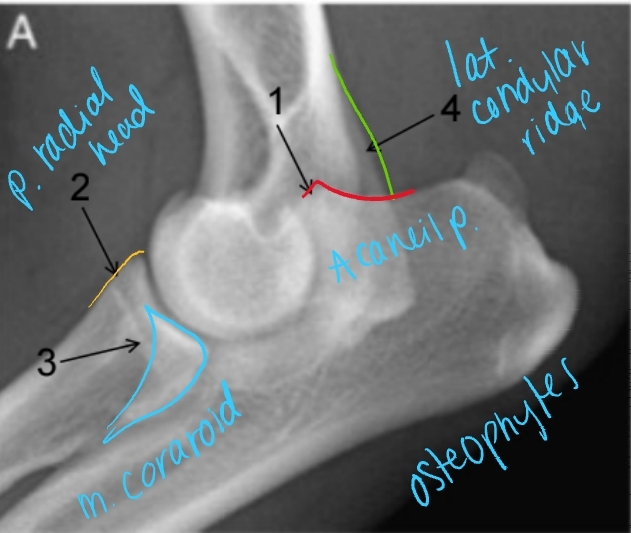

Medial Compartment and Coronoid Disease

Growing/developmental disease, Bilateral

Et: Growth incongruency radius/ulna, abnormal joint stress, pressure on medial coronoid of ulna

Sig: Large breed dogs, Labs, Bernese Mountain Dog, Male > Female, 6-18 months

Cs: OA, Lameness with ambulation, Decreased ROM of elbow joint, Pain(PE/palpation), Minimal joint effusion, Muscle atrophy

Dt: Lateral, AP, flexed, Crlat-oblique

Rads: Osteophytes(back of elbow), Effusion, Subtrochlear sclerosis, Joint incongruity

CT: Most sensitive